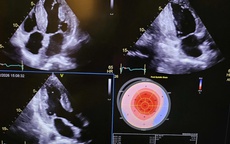

Người dân hào hứng tầm soát sức khỏe hưởng ứng Ngày Thế giới Phòng chống Đột quỵ

Sống khỏe

Hưởng ứng Ngày Thế giới Phòng chống Đột quỵ 29/10, rất nhiều người dân Hà Nội đã đến Tượng đài Lý Tự Trọng tham gia chương trình tầm soát và tư vấn sức khỏe miễn phí.